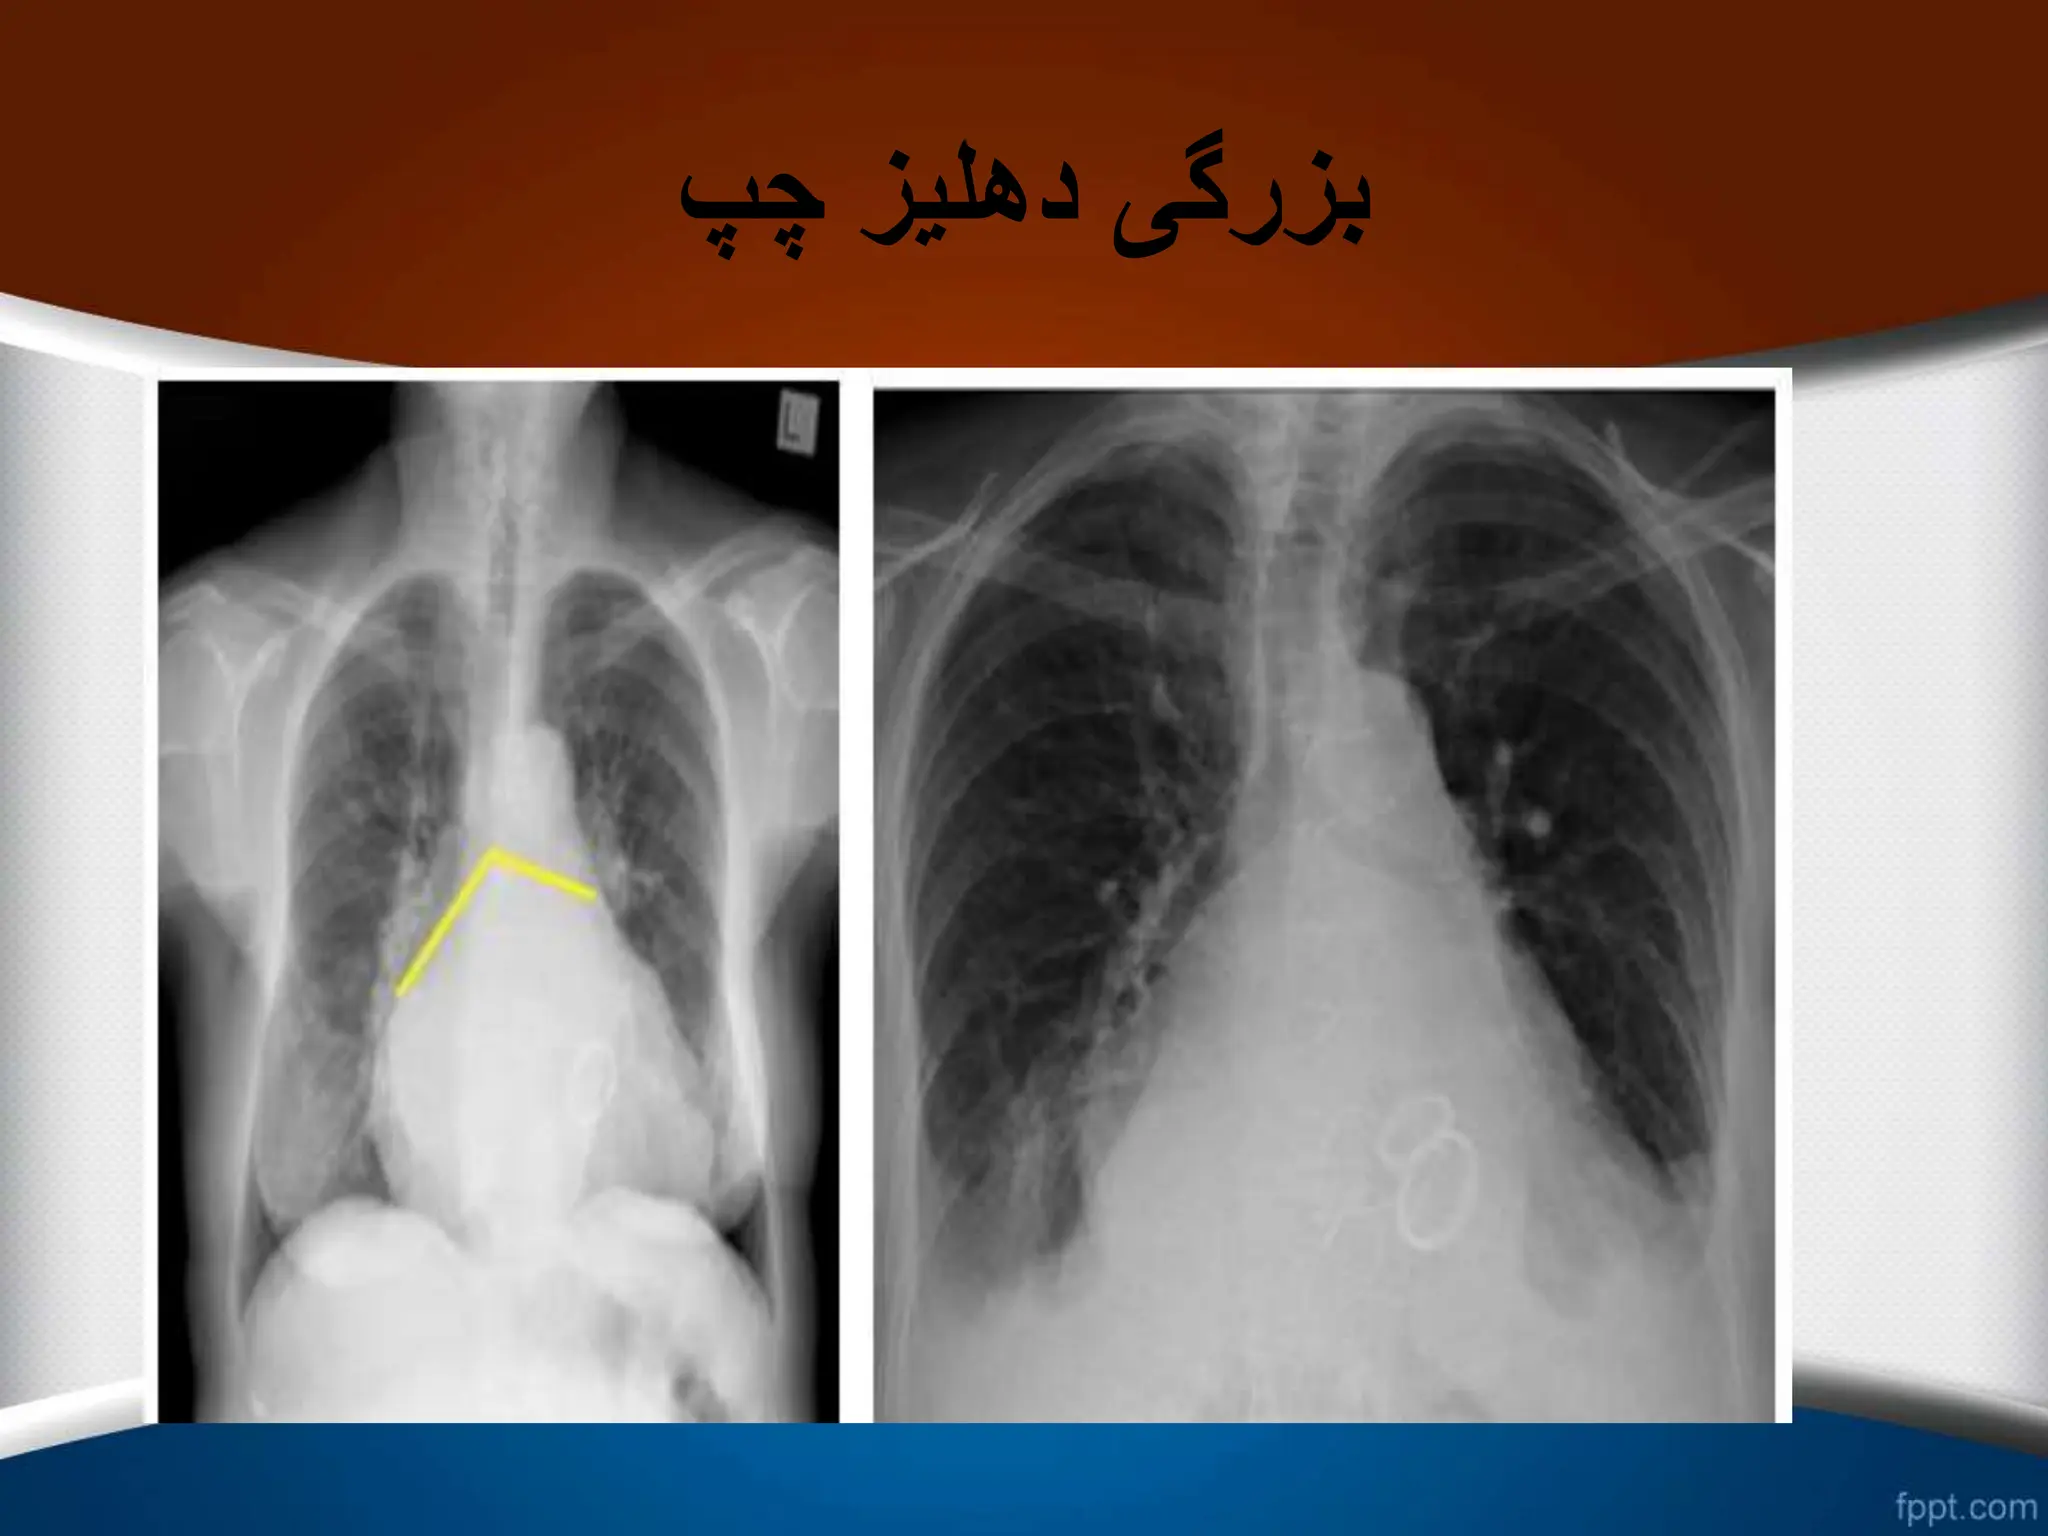

‫چپ‬ ‫دهلیز‬ ‫بزرگی‬